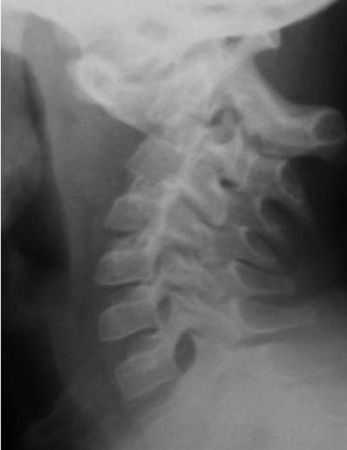

Атланто-аксиальная нестабильность при аномалиях развития биомеханически хорошо объяснима неполноценностью связочных или костных структур. Она проявляется чаще всего в виде смещения CI кпереди со сдавлением спинного мозга (рис. 5.1).

А – боковая рентгенограмма. Полное смещение атланта кпереди и вниз.